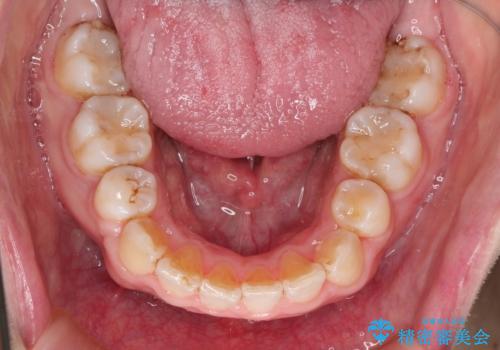

- ガタガタと出っ歯を主訴に来院されました。

上下左右の歯を1本ずつ、合計4本抜歯してワイヤーにて矯正治療をすることとなりました。

前から4番目の歯を抜歯することが多いのですが、右上の前から5番目の歯が神経の治療済みであり、こちらの歯を抜歯する計画としました。

通常より治療期間を要しましたが、健康な歯を残すことができました。